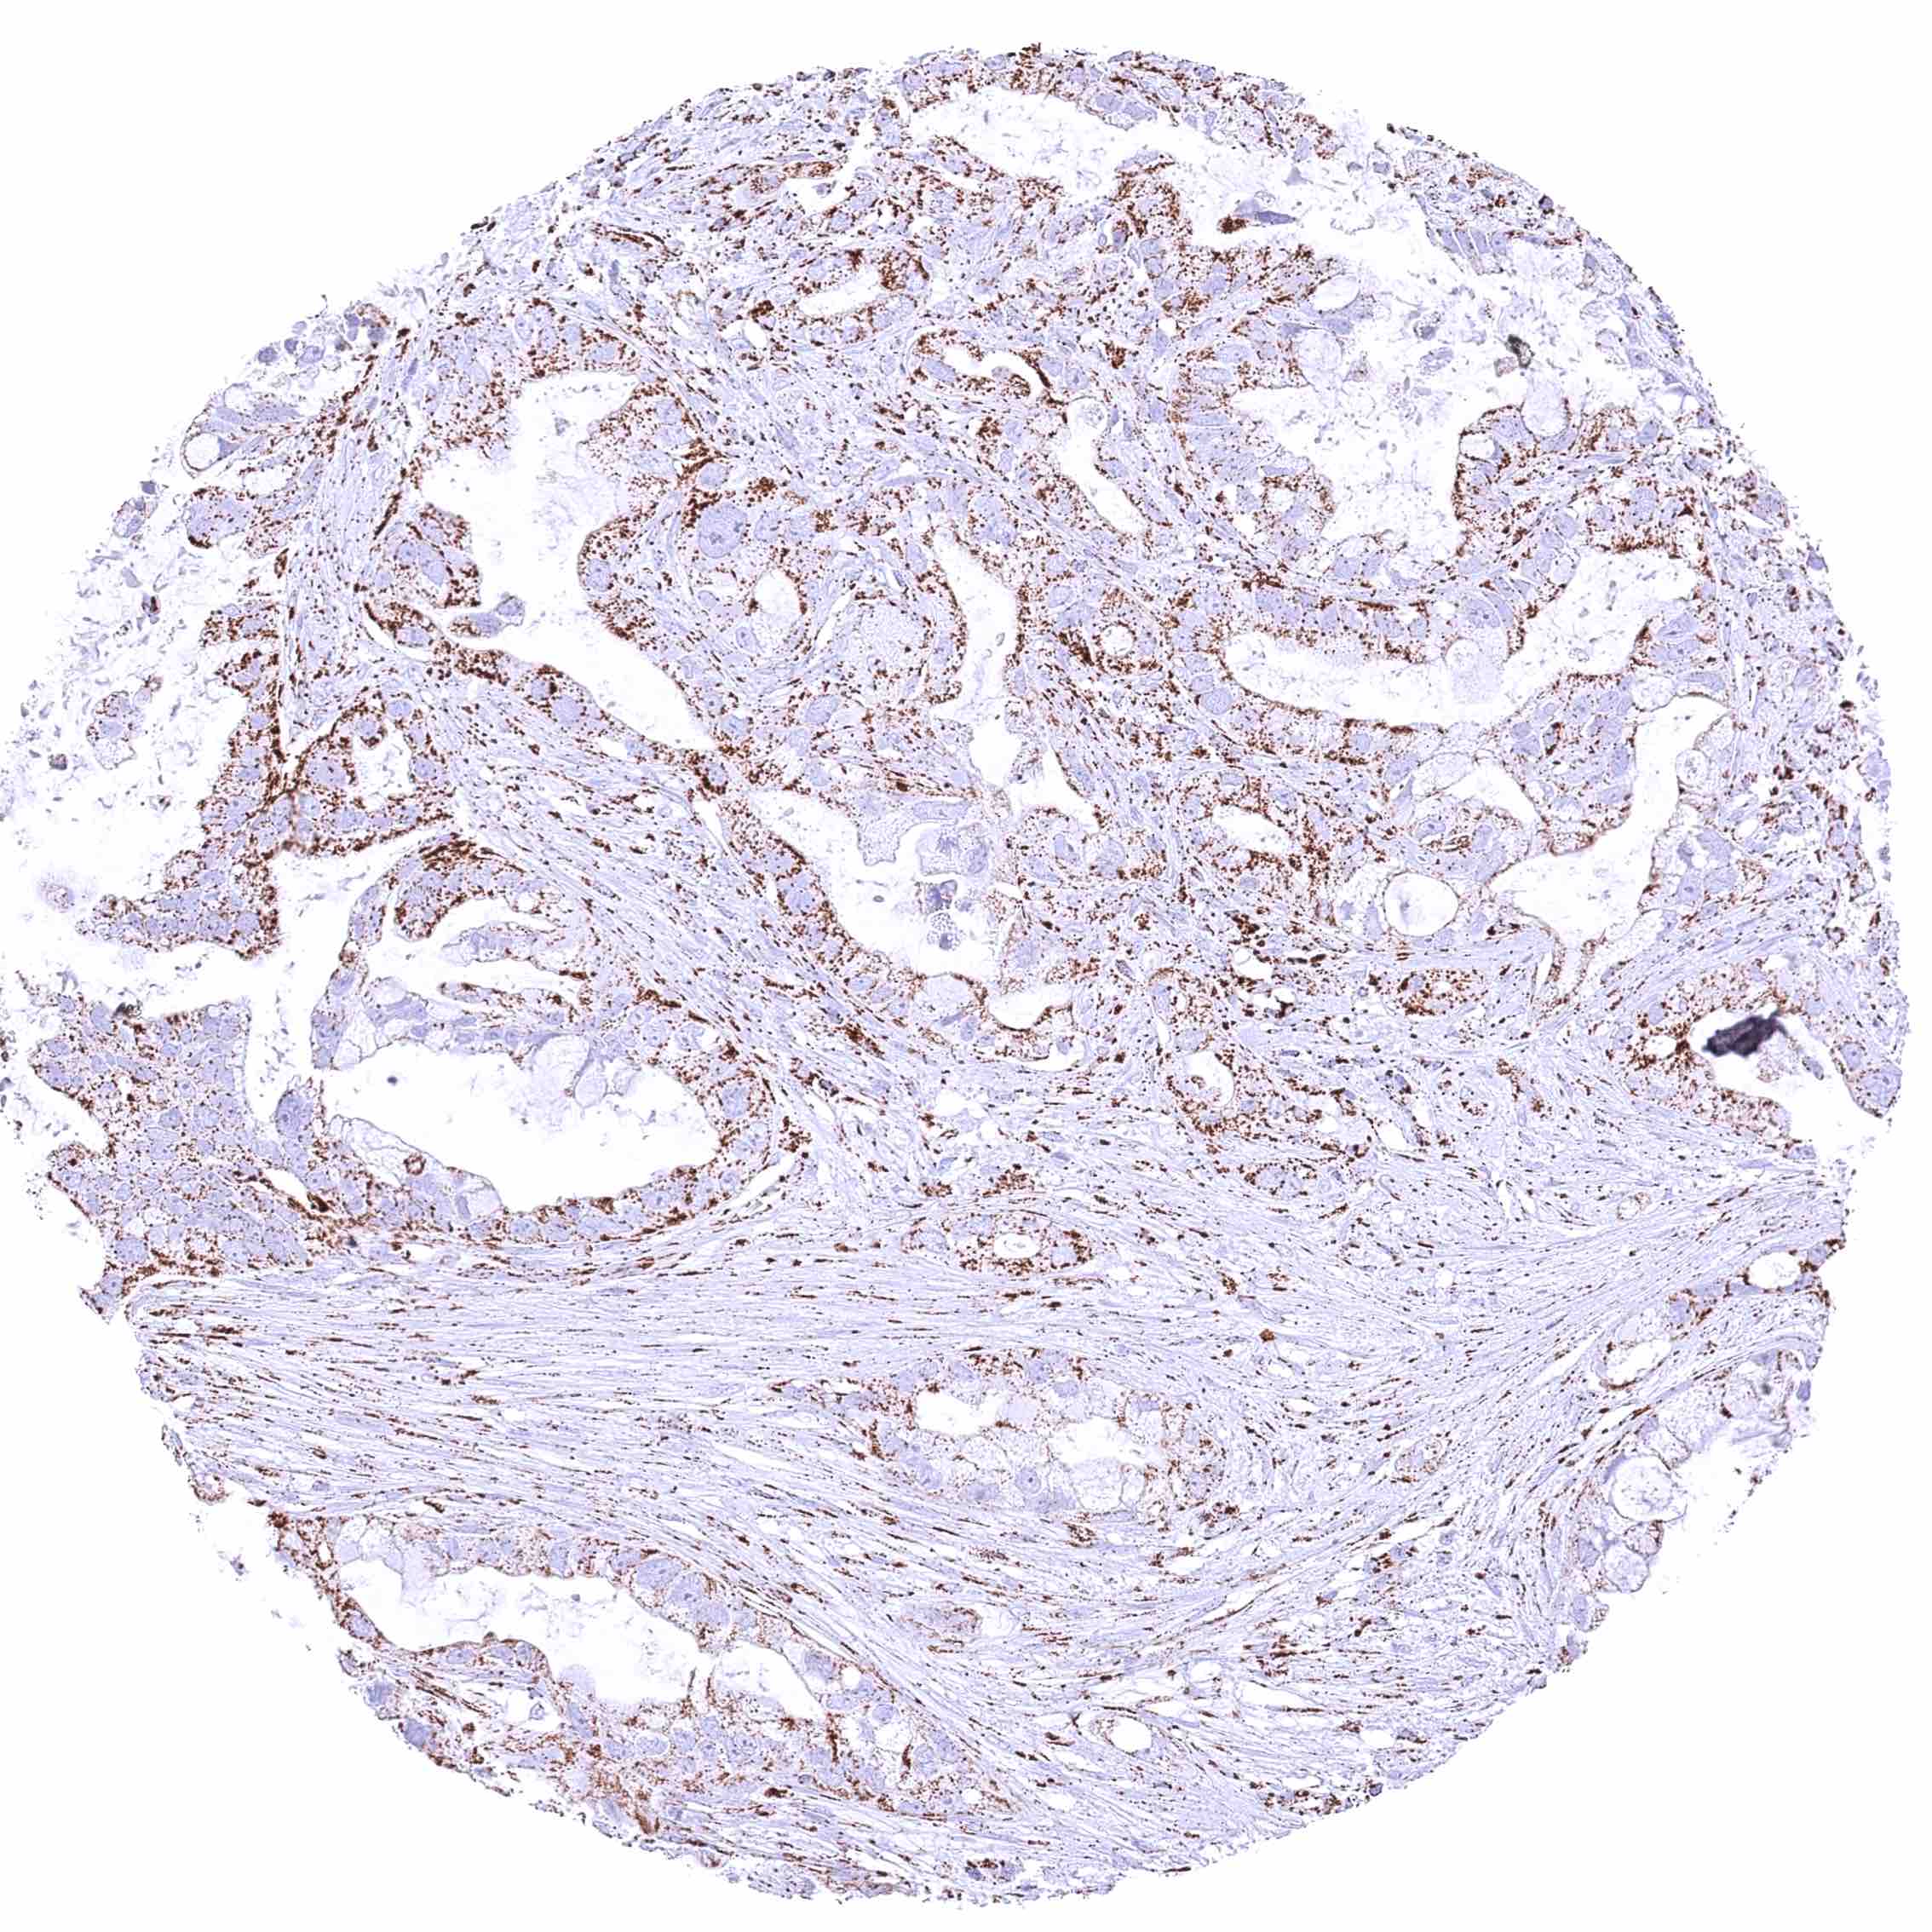

Pancreas – Ductal adenocarcinoma with weak cytoplasmic ATP5J immunostaining of tumor cells. .jpeg